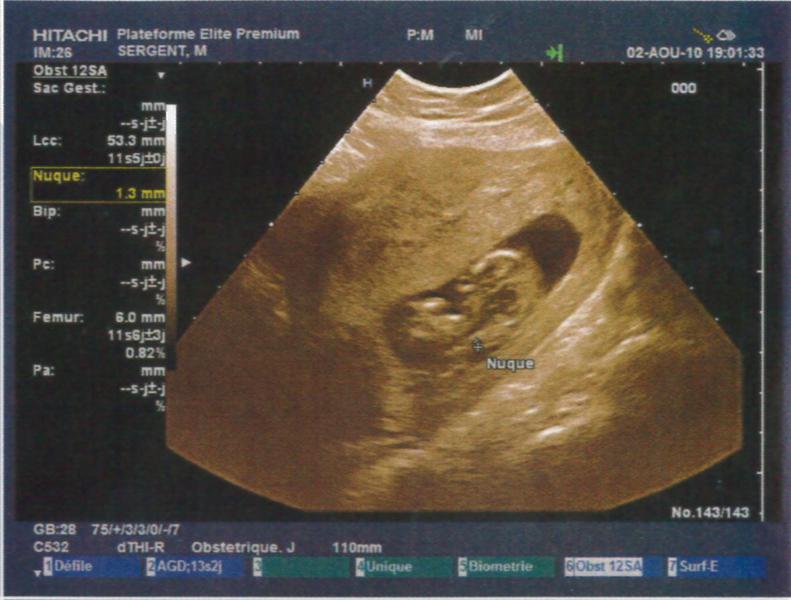

Je suis à 12SA soit 10SG, j'ai fait mon écho hier soir et tout va super bien !!! Je suis trop heureuse je vais vraiment pouvoir vivre ma grossesse à fond !! La nuque est parfaite, à vérifier par le test de la trisomie la semaine pro en même temps que la déclaration !!

Je vous met les photos des échos mais je trouve que l'on ne voit rien par rapport aux superbes images que nous avons vues !! Mais c'est pas grave, on a un super souvenir quand même !!

• echo1.jpg

echo1.jpg

53.6 KB · Affichages: 70